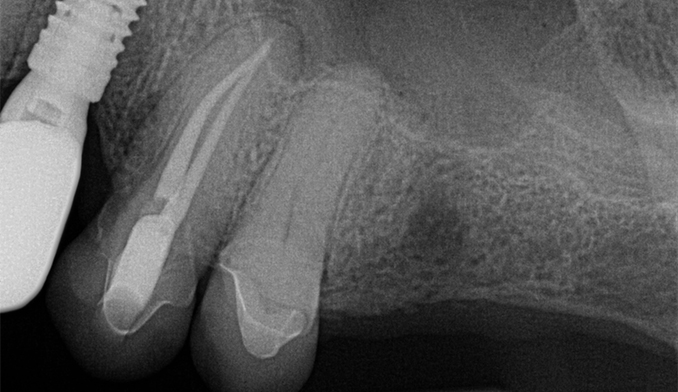

Molar Extraction, Bone Grafting, and Implant Placement

The patient’s lower right molar was severely damaged and could not be saved. After removing the tooth, we performed bone grafting to preserve the bone structure, ensuring a strong foundation for future treatment. Four months later, after proper healing, a dental implant was placed to restore function and maintain jaw health.